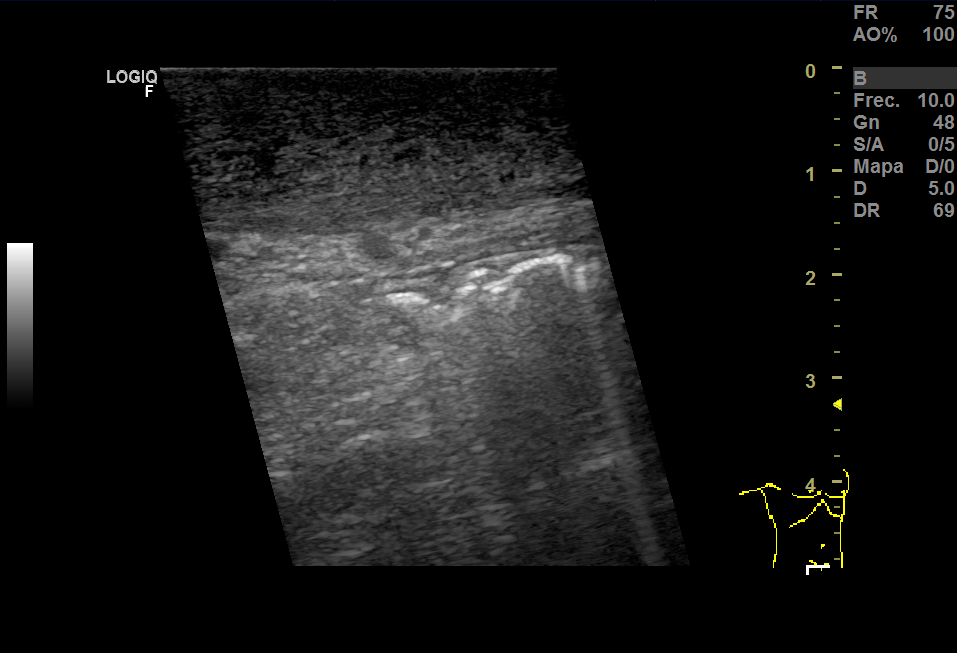

Realizamos una ecografía en Centro de Salud donde vimos que había una herniación derecha y aumento del grosor del tejido celular subcutáneo y, en el espesor, una imagen anecoica que no sabíamos bien a qué podía corresponder.

En la urgencia, realizaron una analítica y encontraron 14.600 leucocitos, PCR 5,13. En Eco testicular, se apreciaron testes de ecoestructura y ecogenicidad normales, epidídimos normales y aumento del grosor del TCSC que impresionaba de celulitis y, en el espesor, una pequeña colección de 15 mm que podía corresponder a absceso o hematoma.